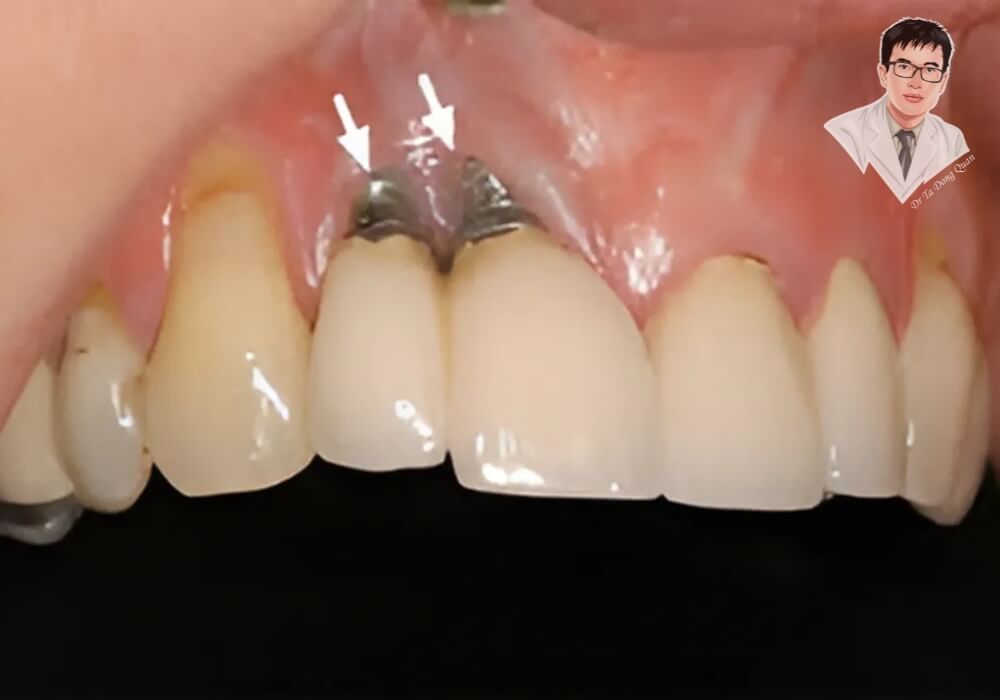

Tụt nướu khiến phần thân hoặc cổ Implant lộ ra ngoài

3. Dấu hiệu nhận biết implant đang bị đào thải qua phim X-quang

Ngoài biểu hiện lâm sàng, bác sĩ sẽ dùng phim chụp để đánh giá mức độ tích hợp của Implant.

Phim X-quang giúp phát hiện:

-

Tiêu xương quanh trụ Implant

Không thấy dấu hiệu bám dính giữa bề mặt trụ và xương hàm

Có khoảng trống quanh trụ, gợi ý tình trạng implant không tích hợp xương

Conebeam CT 3D là công nghệ chẩn đoán chính xác, giúp xác định mức độ tổn thương để can thiệp sớm. Đây là bằng chứng khách quan nhất để xác nhận tình trạng implant bị loại bỏ khỏi xương.